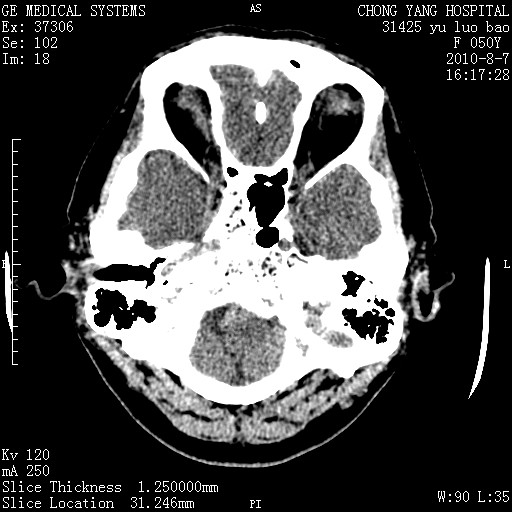

右侧桥小脑角区占位--听神经瘤,建议增强或mri检查。

右侧桥小脑角去等密度占位,右侧内听道扩大、骨质吸收,考虑:右侧听神经瘤,建议增强检查。

右侧内听道扩大、骨质吸收,中脑受压左移,考虑:右侧听神经瘤,建议增强检查。支持!

右侧桥小脑角区等密度占位,内耳道扩大,听神经瘤